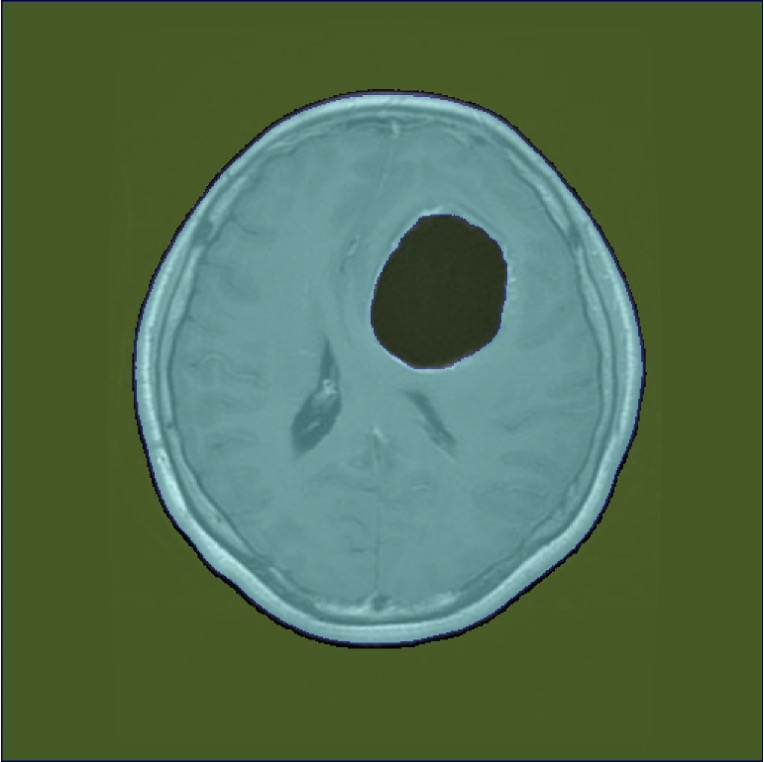

Figure 3: Sample outputs from various datasets showing regions of interest generated from SAM2.

Figure 3 shows the regions of interest generated by SAM2 for various datasets.